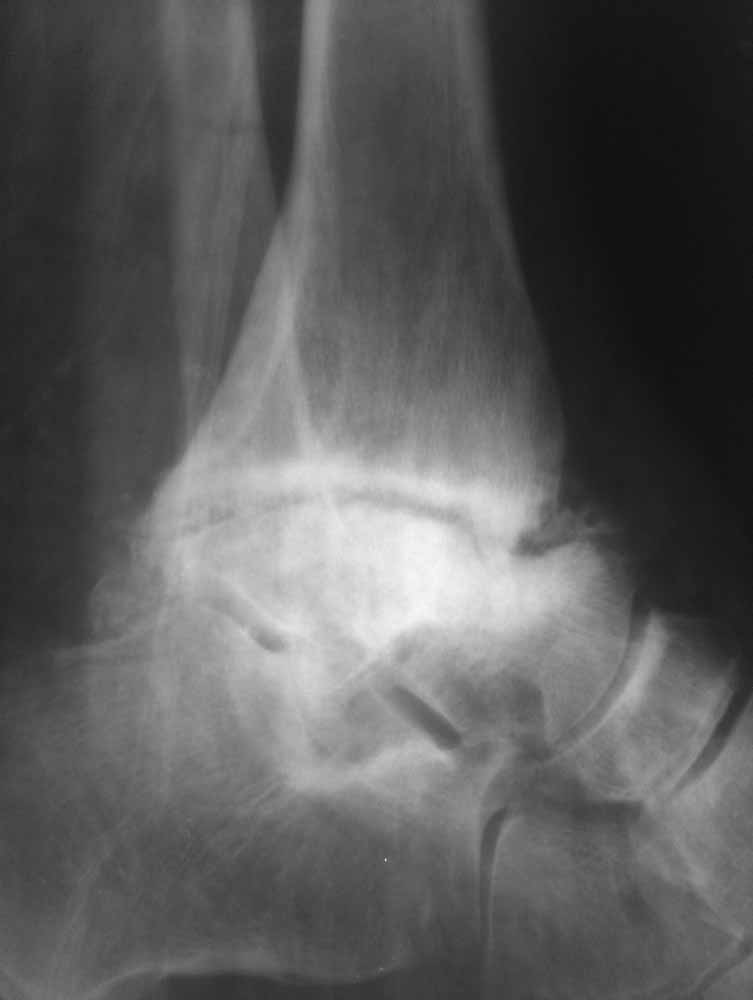

Опять прошу прощения за качество фото, но принципиальные моменты мне кажется, что видны.

Из того, что я вместе с лучевыми диагностами разглядел - нельзя исключить остеомиелит (?) - есть краевая реакция, куча элементов, похожих на секвестры. Смущает полное отсутствие местной и системной реакции - к анализам не придраться.

Наверное здесь имеется асептический некроз таранной кости с патологическим внутренним подвывихом стопы на фоне подагрической артропатии.

Прогрессивное разрушение скелета и характерную деформацию можно увидеть при нейропатической артропатии или Charcot arthropathy.

Артропатия встречается во всех суставах, иногда двухсторонняя, но сложной деформации подвергаются только нагружаемые суставы. Нейропатия в основном связана с развитием диабета, хотя могут быть другие причины (подробный список предоставил др.Gofman).